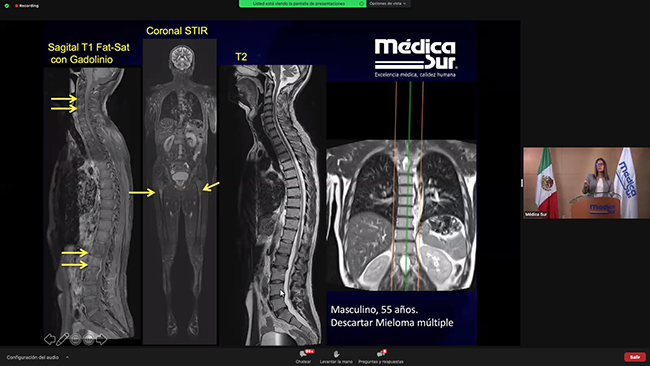

Por primera vez se llevó a cabo el 3 y 4 de febrero de 2022 el Congreso de Resonancia Magnética, organizado por el departamento de Resonancia Magnética de Médica Sur en formato virtual.

Se presentaron 26 conferencias y 2 talleres de casos clínicos, todos impartidos por médicos, residentes y adscritos de Médica Sur y de otras instituciones. Los temas principales que se abordaron fueron los usos de la Resonancia Magnética en: Corazón, Mama, Neurología, Sistema músculo esquelético, Patología oncológica y Abdomen / pelvis.

16:10 - 17:00 · Taller de casos clínicos